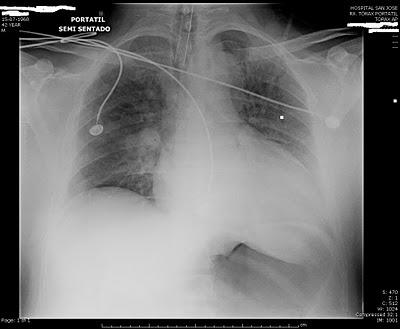

Hoy pudimos conocer por medio del Sofware Synapse,las placas de Rayos y scaner tomado al paciente que confirman el daño cerebral

Puedes ver las placas más abajo.

Se aprecia un aparente opacidad perihiliar ¿neumonia por aspiración?